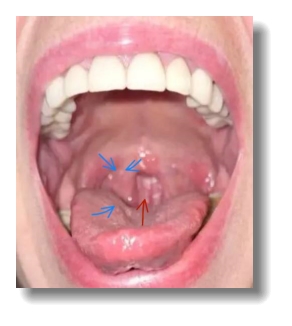

Рис. 3. До процедуры. Гранулёзная форма гипертрофического фарингита (увеличенные гранулы и вязкий слизистый налёт на них) |

Рис. 4. После процедуры. Гранулы удалились, налёта нет, остаётся отёчность гранулы и задней нёбной дужки справа после проведения процедуры (5-е сутки) |